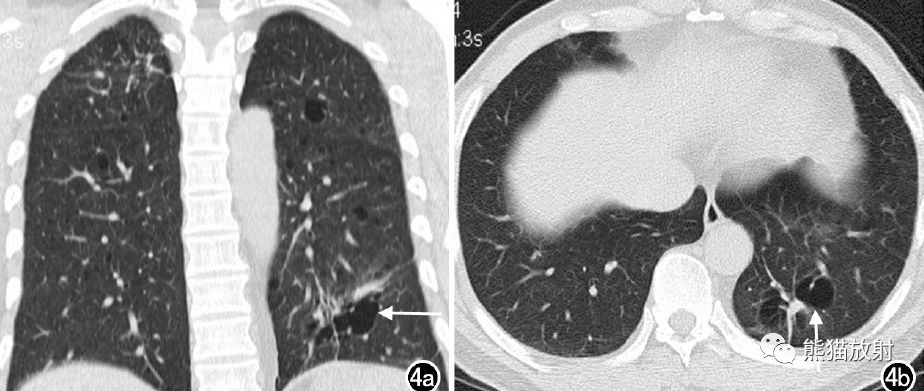

左下肺囊腔类肺癌(低分化腺癌)。冠状面重建图像示右上肺条索影及小结节影,边缘清晰,为结核灶;左下肺囊腔类病灶,形态不规则,见血管影穿行;轴面图像示左下肺不规则形态囊腔,无壁,粗大血管穿行其中。 医学百科网 | YxBaike.Com